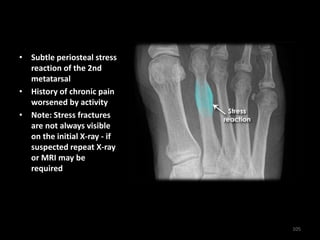

• Subtle periosteal stress

reaction of the 2nd

metatarsal

• History of chronic pain

worsened by activity

• Note: Stress fractures

are not always visible

on the initial X-ray - if

suspected repeat X-ray

or MRI may be

required